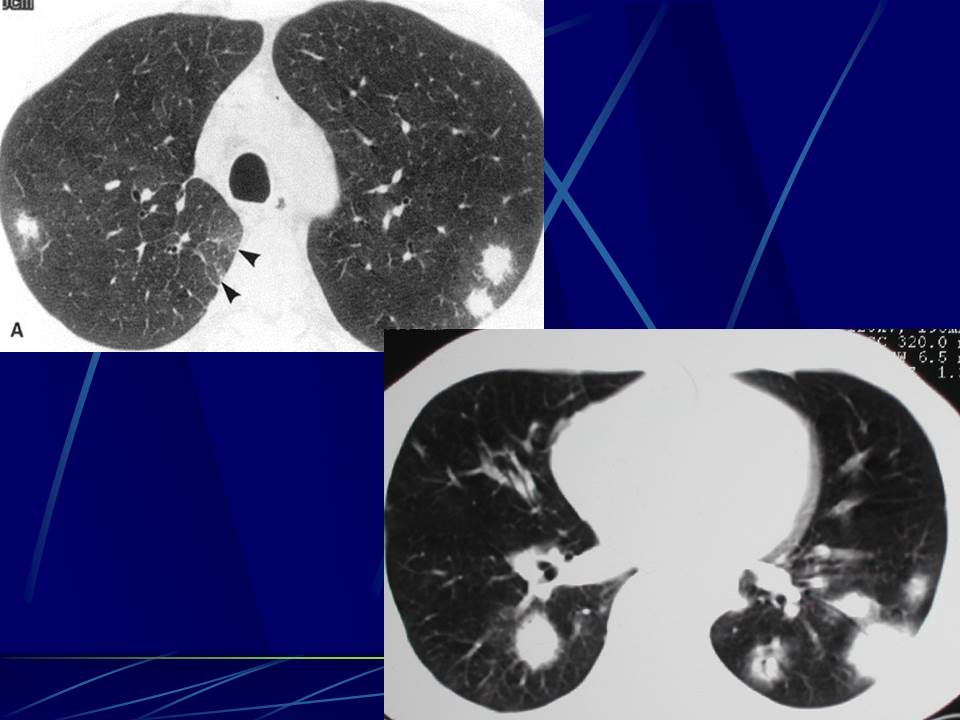

肺部真菌感染影像学分析